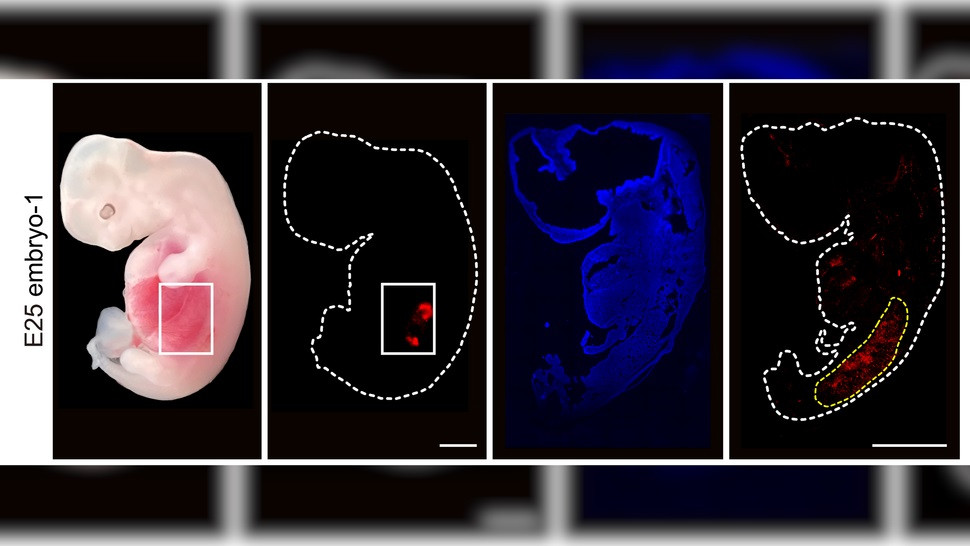

| Mô phỏng cho việc đưa tế bào gốc của người vào phôi lợn. (Ảnh: J. Wang và cộng sự/Tế bào gốc tế bào 2023.) |

Nhóm nghiên cứu đã cấy 1.820 phôi khảm vào 13 con lợn mẹ thay thế, sau đó chấm dứt thai kỳ và trích xuất phôi khoảng một tháng sau đó. Trong số này, 5 phôi chứa thận giai đoạn đầu được tạo thành từ khoảng 50% đến 60% tế bào người và có "cấu trúc bình thường" cho giai đoạn phát triển này. Chúng chứa các tế bào mà cuối cùng sẽ trở thành niệu quản, cấu trúc giống như ống nối thận với bàng quang.